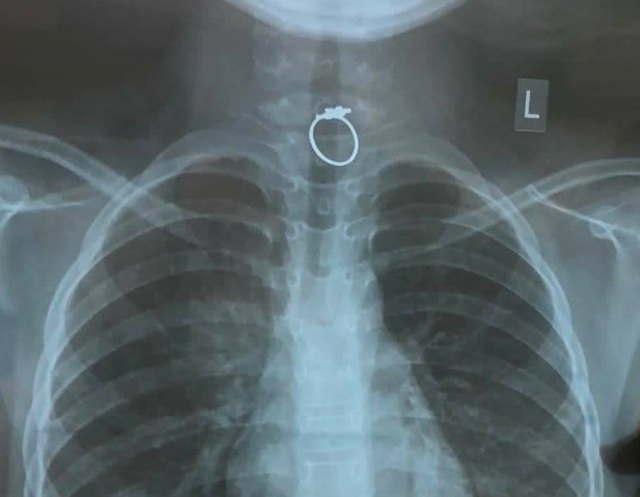

Chiếc nhẫn nằm chắn ngay vị trí 1/3 trên thực quản khiến bé bị nghẹn và khóc nấc liên tục

Bác sĩ Lê Đức Lộc, khoa Tiêu hóa đã phối hợp cùng ê kíp gây mê đang trực Tết khẩn trương can thiệp cho bệnh nhi. Trên hình ảnh camera nội soi, bác sĩ phát hiện, dị vật là chiếc nhẫn nằm chắn ngay vị trí 1/3 trên thực quản. Chiếc nhẫn mắc kẹt ghim chặt niêm mạc khiến bé bị nghẹn và khóc nấc liên tục.